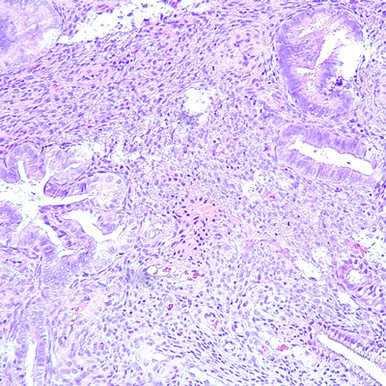

In this online program, you’ll encounter the latest discoveries and diagnostic challenges in gynecologic pathology, focusing on biopsies, resections, and gestational trophoblastic neoplasia. You’ll examine commonly encountered specimens such as endometrial and cervical biopsies, as well as the complex mesenchymal lesions that often pose diagnostic difficulties.

Organized by anatomic location and neoplasia subtypes, the Gynecologic Pathology course — part of our Masters of Pathology Series — will help you build a structured and practical approach to interpreting a wide range of gynecologic specimens. It’s continuing medical education that:

- Demonstrates how to integrate a wide array of immunohistochemical stains and molecular assays alongside morphologic features in surgical pathology